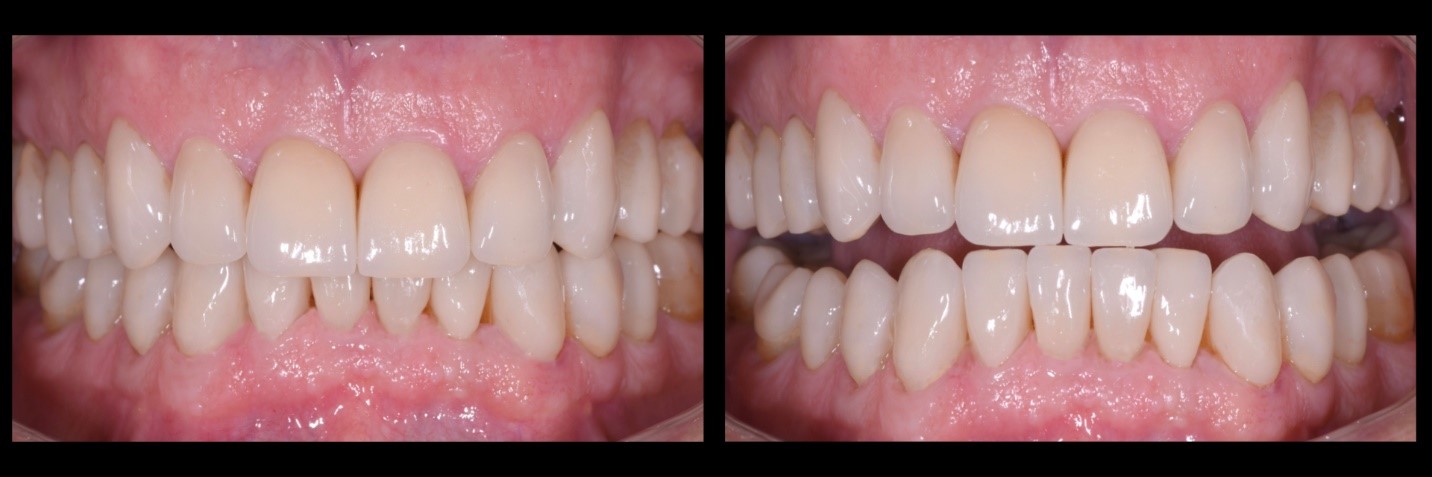

Fig. 8a e 8b

Integrazione dei restauri in disilicato di litio monolitico all’interno del sorriso del paziente in massima esposizione, rispetto alla situazione iniziale.